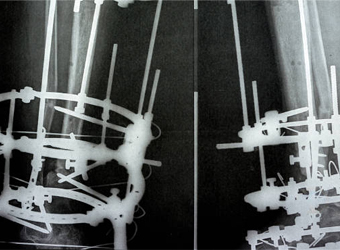

Dr. Suhas Shah has been practicing as an orthopedic surgeon with super specialization in Ilizarov surgery since last 16 years. He is visiting as an Ilizarov specialist all over Maharashtra and has done more than 1400 surgeries in this specialty till now. I have been a faculty member during various Ilizarov courses & workshops held all over India.We now have a center for total Orthopedic care under one roof.

Cosmetic limb lengthening is a surgical procedure that is done for aesthetic purposes rather than medical necessity. It involves using the Ilizarov method, an external fixator...

Deformity correction using the Ilizarov method is a surgical procedure that involves the use of an external fixator to realign bones and joints in the body.

Polio is a viral infection that can lead to muscle weakness and paralysis. In some cases, it can cause significant deformities of the legs, including limb length discrepancy...